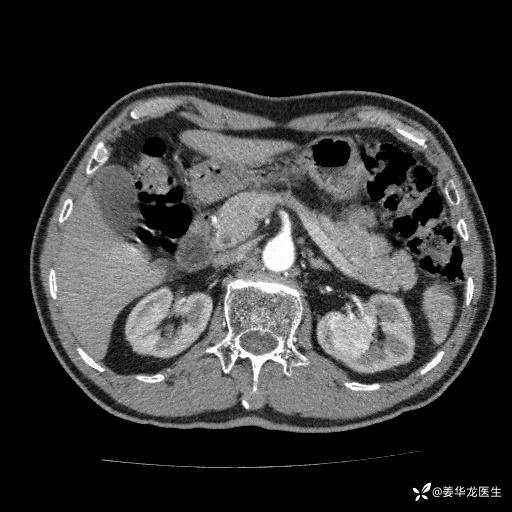

左肾中心型肾门部肿瘤39mm×34mm×36mm,右肾GFR25ml/min,部分切还是全切?

患者75岁老年男性,体重50kg,无高血压、肾病、糖尿病等基础病,检查发现左肾中心型肾门部肿瘤,右肾GFR只有25ml,无肉眼血尿,无镜下血尿。入院验血常规检查均正常,包括肾功能,肌酐102.7umol/L.

二、左肾肿瘤与左肾集合系、左肾动静脉关系密切,左肾部分切除术可行吗?成功率有多大?成功部分切后,肾功能还有多少?

三、患者无任何基础病,为什么右肾GFR只有25ml/min,反尔有肿瘤的左肾GFR达38.8ml/min?